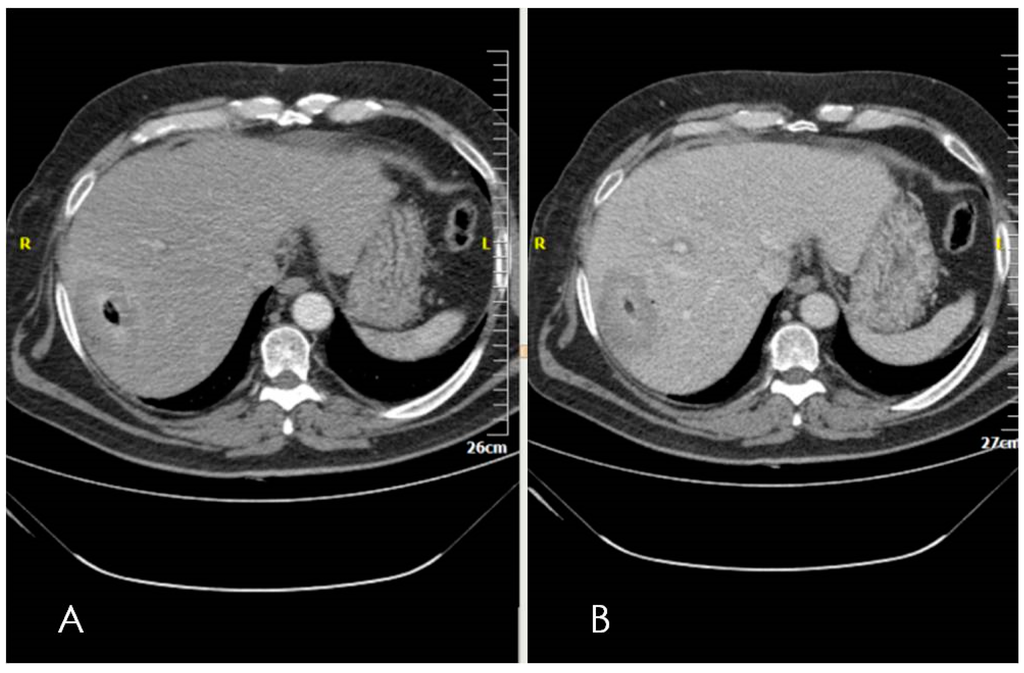

3. Ultrasounds

4. Computed Tomography (CT)